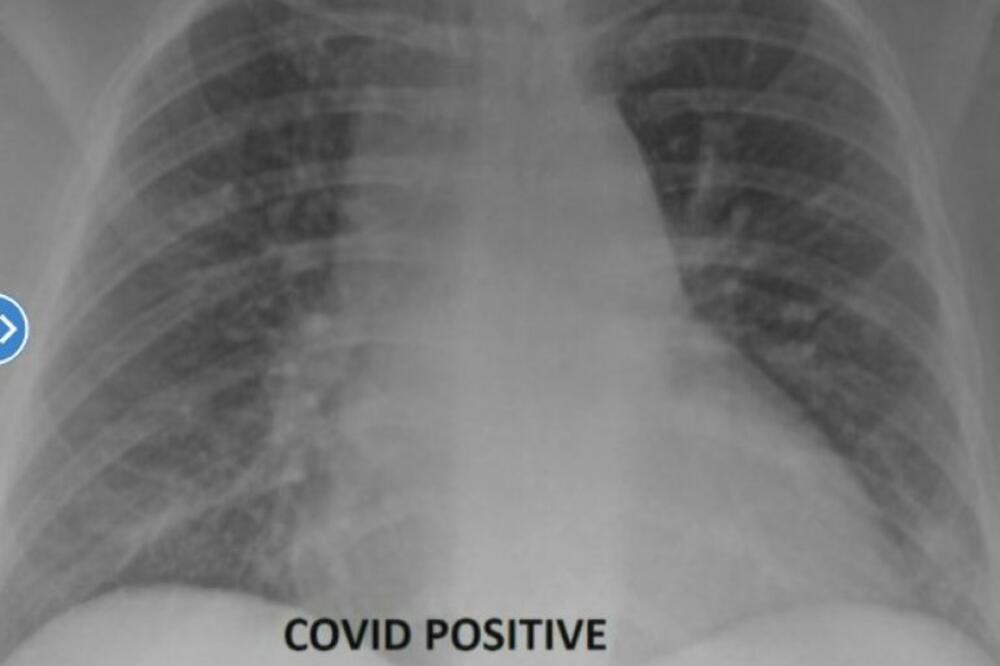

Kada su u pitanju oni pacijenti koji su neophodne doze vakcina primili, slika njihovih pluža daleko je jasnija i povoljnija.

“Snimak vakcinisanih pacijenata zaraženih pokazuje više protoka vazduha, pri čemu je veći deo pluća obojen u crno, što znači da nema ili ima izuzetno mala oštećenja”, rekao je doktor.

“Ako imate vakcinisanog pacijenta koji dođe u hitnu pomoć sa prodornom infekcijom, koji možda ima kratak dah i uradimo CT skeniranje, oni nisu ni približno tako loši kao nevakcinisani pacijenti”, dodaje doktor Sem Durani.

Gledajući slike i štetu koju virus može da ostavi na plućima, dr Durani opravdava time što ljudi dobiju svoju neophodnu dozu koja ih u velikoj meri čuva od teške kliničke slike.

“Vakcina deluje izuzetno dobro i sprečava da virus napreduje do upale pluća ili da se infiltrira u pluća. Kada dobijete dozu, možete se malo razboleti, ali na kraju vaše telo prepozna virus, napadne ga i vi ne budete hospitalizovani, ne stavljaju vas na respirator. Vakcina je veoma efikasna”, istakao je doktor Durani.